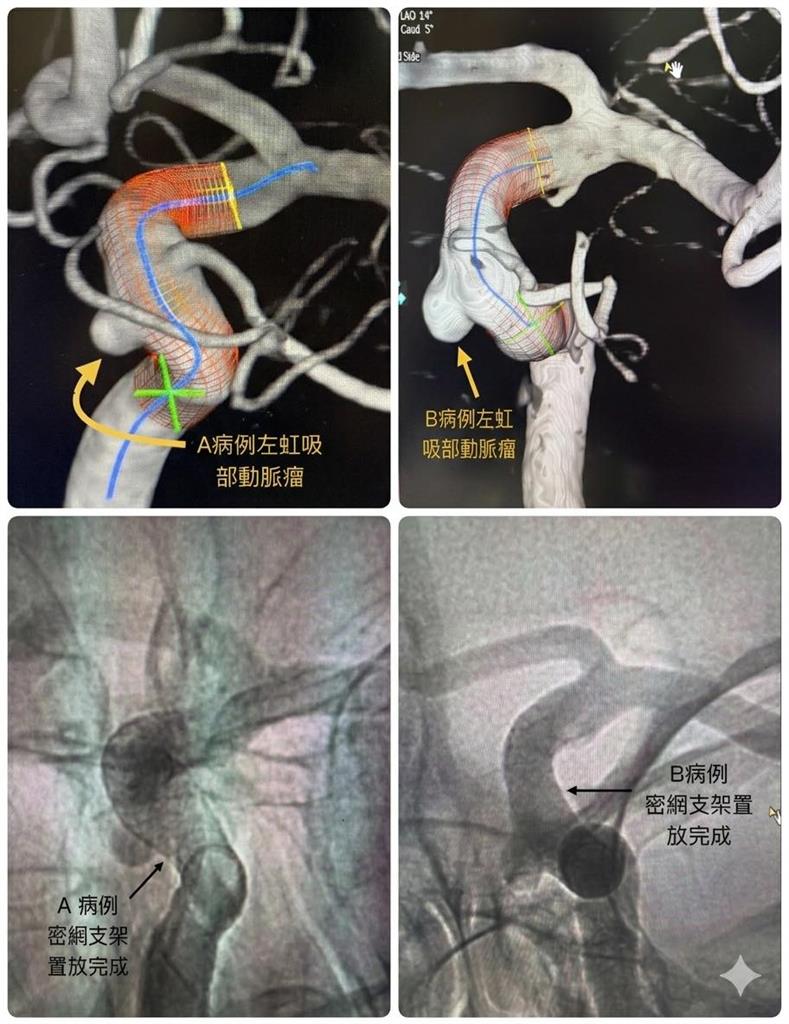

一起看似離奇的醫療案例,近日在醫界引發關注。聯新國際醫院神經醫學中心執行院長陳啟仁分享,兩名年近50歲的男性友人,因為出現「頭脹脹的」不適感,分別前往檢查,沒想到竟在腦部相同位置發現動脈瘤,更巧的是,兩人過去曾在同一間公司任職,而他們的前老闆也疑似因動脈瘤破裂40多歲時猝逝,巧合程度讓人震驚。